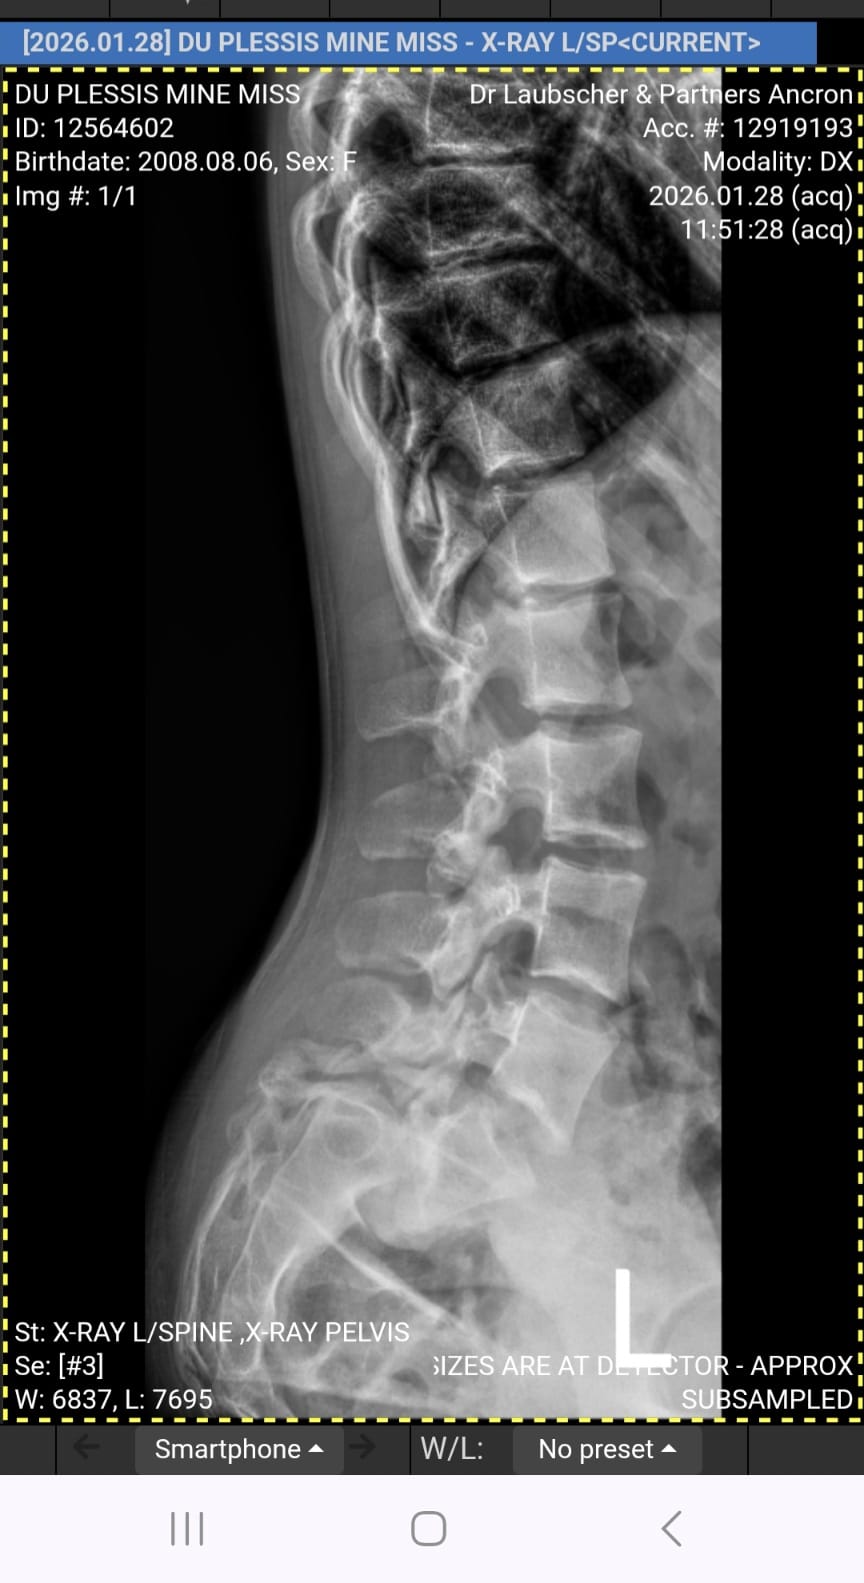

Die sonar van haar rug. Foto verskaf

Nadat sy na ’n ortopediese spesialis verwys is, het X-strale in Januarie die erns van haar toestand bevestig. Haar L5-werwel het heeltemal gegly en is nou onder die S1-werwel, net bo die stuitjie.

Volgens Pienaar glo dokters dat die toestand ’n rol gespeel het in die ontwikkeling van haar ruggraatprobleme. Daar word vermoed dat sy met spondilolistese gebore is, ’n toestand waarin een werwel vorentoe gly oor die werwel onder dit.

Met verloop van tyd het die toestand progressief vererger en nou gevorder tot spondilopiose, die ernstigste vorm van die versteuring, waar die werwel heeltemal uit sy posisie gegly het.

As die werwel oormatig gly, kan die been op ’n senuwee druk, wat pyn veroorsaak. Oor die algemeen word ruggraatbene van die lae rug aangetas.